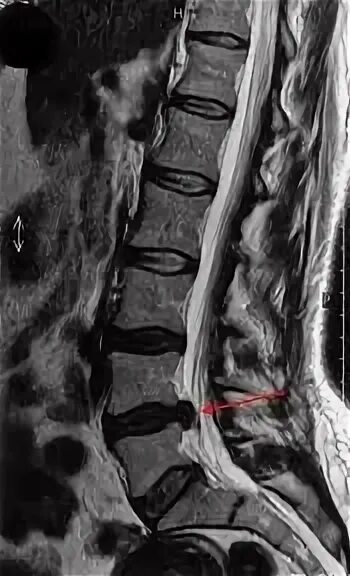

Грыжа диска мрт